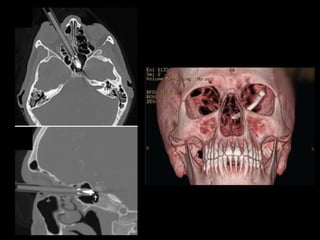

FRACTURA NASO-ÓRBITO-ETMOIDAL

(NOE)

• Golpe en nariz y transmisión posterior

etmoidal (contrafuertes maxilares mediales)

• Fractura del tercio medio facial que involucra

hueso etmoides (lámina perpendicular,

papirácea y cribiforme), propios nasales y

apófisis ascendentes de maxilares.

• Es la zona de la cara con menor resistencia a

fuerzas de fractura.

NOE

• Clasificación de Markowitz

– Tipo I: segmento central único, sin compromiso del

canto interno.

– Tipo II: segmento central conminuto, sin compromiso

del canto interno.

– Tipo III: segmento central conminuto, con

desinserción del canto interno.

FRACTURA NASO-ÓRBITO-ETMOIDAL (NOE) • Golpeen nariz y transmisión posterior etmoidal (contrafuertes maxilares mediales) • Fractura del tercio medio facial que involucra hueso etmoides (lámina perpendicular, papirácea y cribiforme), propios nasales y apófisis ascendentes de maxilares. • Es la zona de la cara con menor resistencia a fuerzas de fractura.

NOE • Clasificación deMarkowitz – Tipo I: segmento central único, sin compromiso del canto interno. – Tipo II: segmento central conminuto, sin compromiso del canto interno. – Tipo III: segmento central conminuto, con desinserción del canto interno.

• #18 The Markowitz and Manson classification system categorizes fractures of the NOE complex according to whether the medial canthal tendon is involved, as follows: In type I NOE fractures, the medial canthal tendon is intact and connected to a single large fracture fragment; in type II fractures, the fracture is comminuted, and the medial canthal tendon is attached to a single bone fragment; in type III fractures, comminution extends to the medial canthal tendon insertion site on the anterior medial orbital wall at the level of the lacrimal fossa, with resultant avulsion of the tendon (Figs 6, 7) (14). Although the tendon itself is not visible at multidetector CT, the radiologist’s report of the degree of comminution of the medial orbital wall at the level of the lacrimal fossa may be helpful for surgical planning of medial canthal tendon repair. Figures 6, 7. (6) Three-dimensional CT images of an adult skull with graphic overlays depict the Markowitz and Manson classification system for classifying fractures of the NOE complex: type I NOE fracture (a), characterized by a single large central fragment with attached medial canthal tendon; type II NOE fracture (b), characterized by comminution without extension to the medial canthal tendon attachment; and type III NOE fracture (c), characterized by comminution through the medial canthal tendon attachment, with resultant tendon avulsion. (7) Three-dimensional CT image of the left medial maxillary buttress in lateral oblique orientation shows a single fracture fragment that includes the lacrimal fossa at the expected insertion site of the medial canthal tendon, findings indicative of a type I NOE fracture. Fractures through the left frontal calvaria, lateral orbital rim, and zygomatic arch also are seen.

• #20 comminuted fracture of the NOE complex with telecanthus and involvement of the bilateral lacrimal fossae (arrows), findings indicative of a type III fracture of the NOE complex with medial canthal tendon avulsion. A fragment of the fractured right medial orbital wall impinges on the right optic nerve